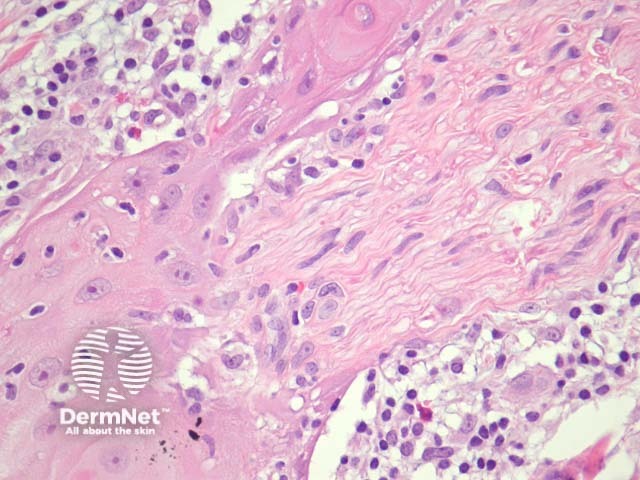

Typical SCC has nests of squamous epithelial cells arising from the epidermis and extending into the dermis (figure 1). The malignant cells are often large with abundant eosinophilic cytoplasm and a large, often vesicular, nucleus. Variable keratinisation (keratin pearls etc) is present (figure 2).

Grading of SCC depends on how easy it is to recognise the characteristics of squamous epithelium (eg. intracellular bridges, keratinisation), pleomorphism and mitotic activity. There is considerable inter-observer variation in grading SCC.